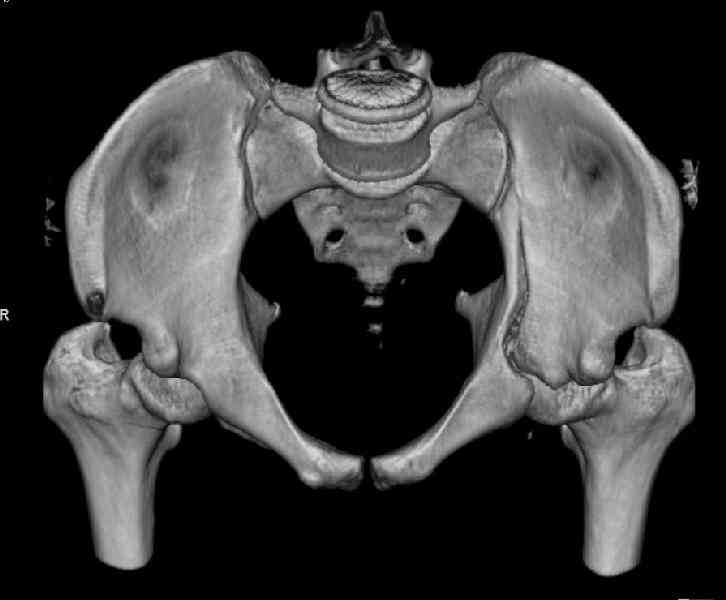

The last two images from the 3-D CT scan certainly makes the fracture look worse than the plan radiographs.

Might have to reconsider my suggestion to leave it alone at this stage.

Ilioinguinal approach would be the best to approach and clean out fracture with recon plate fixation as suggested by Dr. Venkatachalam.

The joint is non-concentric as the head appears to be either "following the caudal segment", or the dome component is displaced from the tethered head... or so it seems... and he's young... so, many fracture surgeons would recommend reduction and fixation.

So we must decide preoperatively which part is the displaced segment?

It's difficult to know from these few selected images which component of the injury (was before and now) should be deemed the "soon to be mobile"

segment. It's my best guess that it is the caudal portion and there exists a healing fracture line somewhere thru the posterior column...one image

suggests it. If true, its early healing/union should be disrupted, and the resultant fragment mobility then allows accurate reduction.

Normal appearing SI joints and a healed posterior column limb... my bet's on caudal segment displacement.